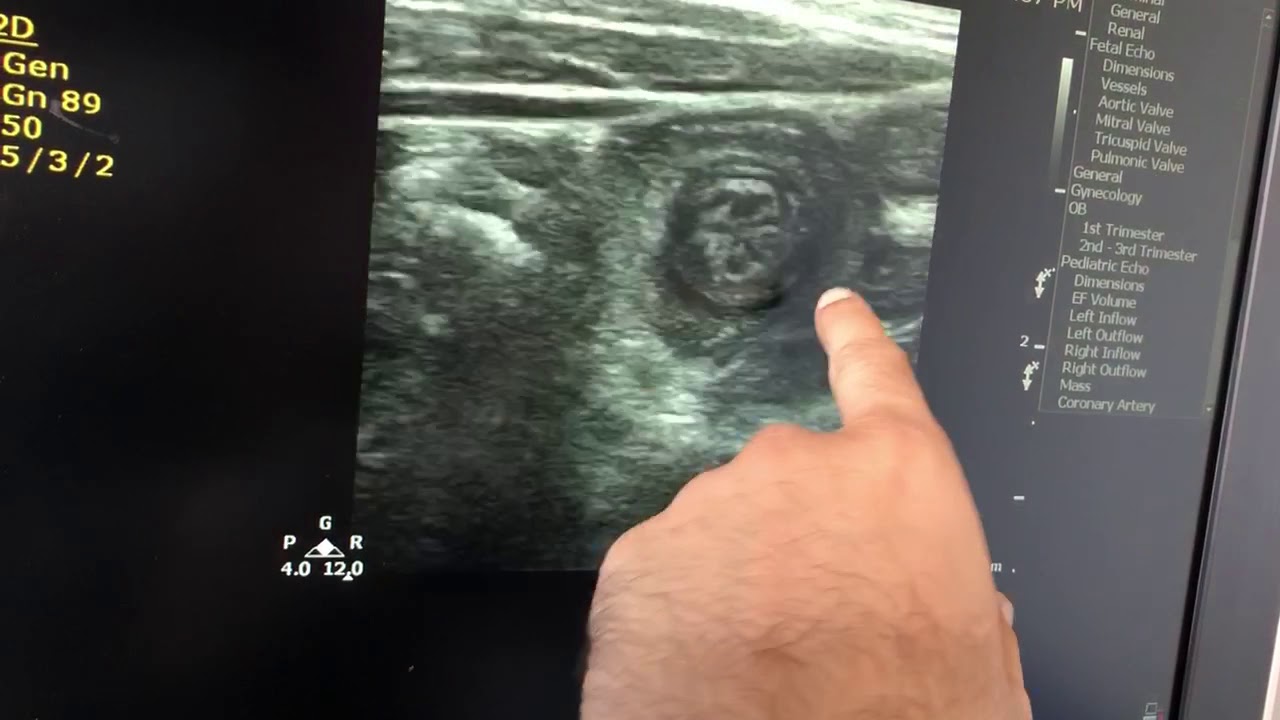

Скачать или смотреть Parasitic infestation with intussusception n inflammed ileum

Parasitic infestation with intussusception n inflammed ileum